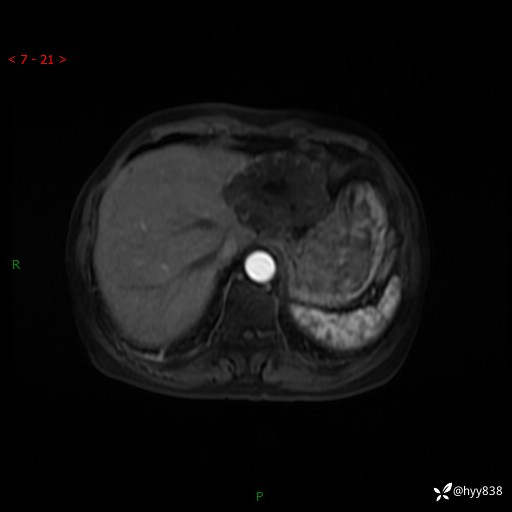

辅助检查:MRI

肝脏MRI平扫(同反相位)

T2WIfs+DWI

增强(动脉期+静脉期+延迟期)